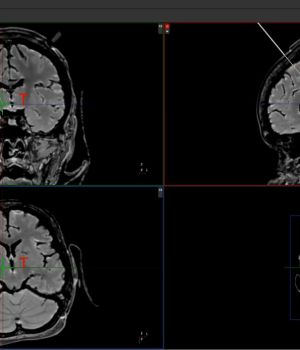

Entwicklung einer Planungssoftware für die Tiefenhirnstimulation - Probabilistische Traktografie

Ziel des geplanten Forschungsprojektes THSpro ist die Entwicklung eines Softwaretools zur Zielpunktplanung für die Tiefe Hirnstimulation mit hohem Marktpotenzial. Aus Messdaten der diffusionsgewichteten Magnetresonanztomografie werden unter Nutzung der probabilistischen Traktografie die neuronalen Faserbahnen im Gehirn rekonstruiert. Anhand dieser neurologisch-funktionalen Daten wird der Zielpunkt der Tiefen Hirnstimulation bestimmt. Sie wird die Genauigkeit der Zielpunktfindung verbessern und so direkt dem Patientenwohl dienen. Die prozessgesteuerten Handlungsabläufe des Planungsvorgangs werden auf Zeit-, und damit Kostenersparnis, optimiert. Die Schulung und Bedienhilfe wird mit einem interaktiven Videointerface effizient realisiert. Eine eigens konzipierte VSEO-Strategie wird Experten und Betroffene helfen sich umfassend zu informieren.

Methoden des maschinellen Lernens werden eingesetzt, um die zeitaufwendigen Berechnungen der probabilistischen Traktografie zu verkürzen. Dies bedeutet einen zeiteffektiveren Planungsvorgang und spart Kosten.